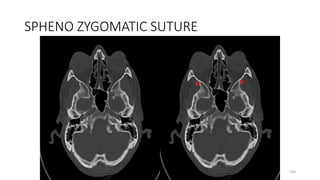

SPHENO ZYGOMATIC SUTURE

GREATER WING SPHENOID